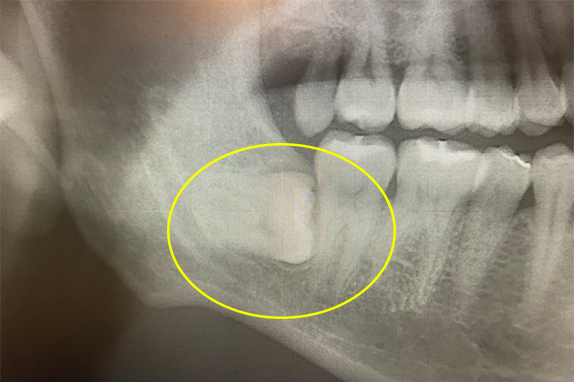

CASE 03 歯周再生療+PDT療法

-

- 主訴

- 右下奥歯から膿が出る(30代女)

-

- 回数期間

- 5回 約8ヶ月

-

- 治療法

- 歯周再生療法+PDT療法

-

- 治療費用

- 約20万円(税抜)

右下奥歯から膿が出るという主訴で来院。歯周再生療法、PDT療法で改善したケースです。

<リスク・副作用>

治療後は痛み、腫れ、痺れなどの副作用が生じる場合があります。症状が再発する可能性があります。